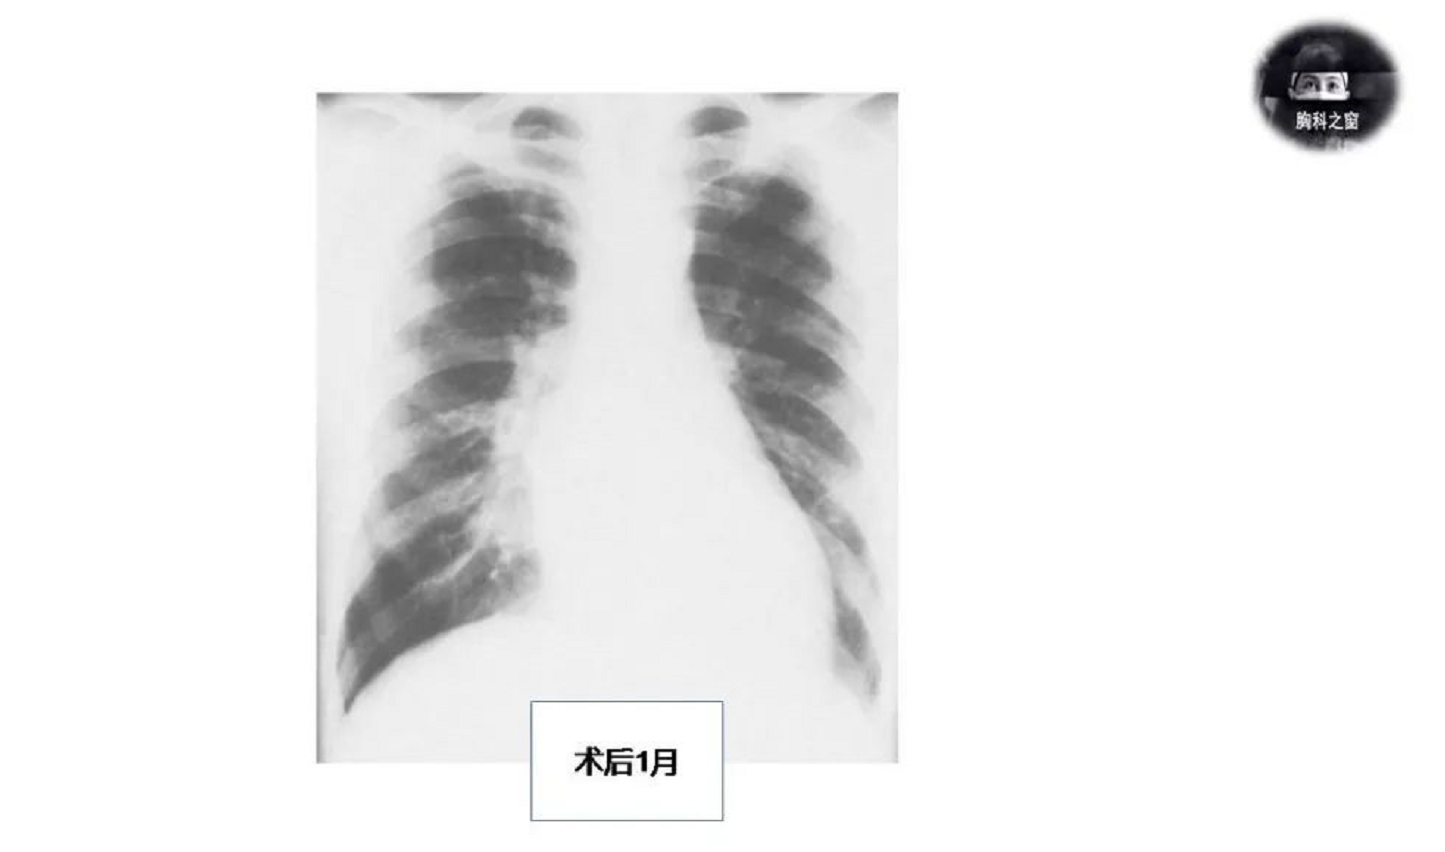

影像学表现

•肺静脉曲张影像表现多种多样

•1.形态:圆形、长管状、分叶状、结节状、肿块状

•2.边缘边界:光滑、清晰

•3.先天性肺静脉曲张常见于外周肺静脉,可类似AVM表现;亦可见曲张闭锁的肺静脉引流至邻近未闭的肺静脉

•4.获得性肺静脉曲张最常见于右下叶,其次是左上叶,扩张的静脉主要位于静脉交界处